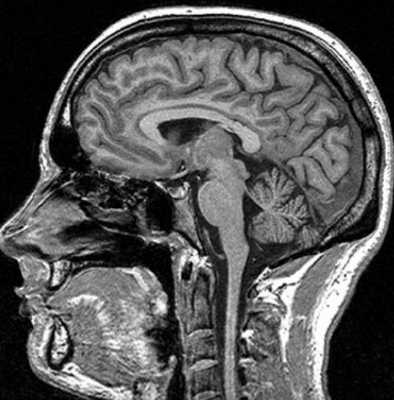

МРТ костей черепа что показывает

Магнитно-резонансная томография базируется на способности магнитного поля изменять состояние атомов водорода в молекулах воды. Процедура информативна относительно мягких тканей, насыщенных жидкостью. Структуры организма с низким содержанием воды на снимках отражаются плохо. МР-томограф фактически «не видит» костную ткань. По этой причине рутинная диагностика переломов включает рентгенографию и КТ (в экстренных, спорных либо сложных ситуациях). При травмах головы стандартное обследование с помощью Х-лучей нередко сочетают с магнитно-резонансной томографией. В зависимости от того, что показывает МРТ костей черепа, дополняют тактику лечения, основанную на результатах КТ. Процедура дает информацию о состоянии мягких структур и влиянии на последние травм.

Показывает ли МРТ перелом черепа?

В основе метода — явление ядерно-магнитного резонанса, свойственное атомам с непарным количеством протонов. Поле, создаваемое установкой, заставляет микрочастицы вращаться по другой траектории. Затем элементы резко переходят в первоначальное положение. Аппарат улавливает возникающие при этом энергетические импульсы и преобразует последние в картинку. Так томограф делает послойные снимки изучаемой области.

Диагностическая ценность магнитно-резонансной томографии высока при травмах сложных структур организма (черепная коробка, позвоночник, сочленения). По результатам сканирования диагностируют не сам перелом, а сопутствующие повреждения (разрывы связок, мышц, компрессию тканей и пр.).

На вопрос «Показывает ли МРТ перелом черепа?», врачи дают отрицательный ответ. При травмах головы методом выбора является компьютерная томография. По снимкам оценивают состояние костей, обнаруживают малейшие повреждения последних, кровотечения. Компьютерная томография особенно информативна в первые 48 часов после получения травмы. В дальнейшем изменения в мозге контролируют посредством МР-сканирования.